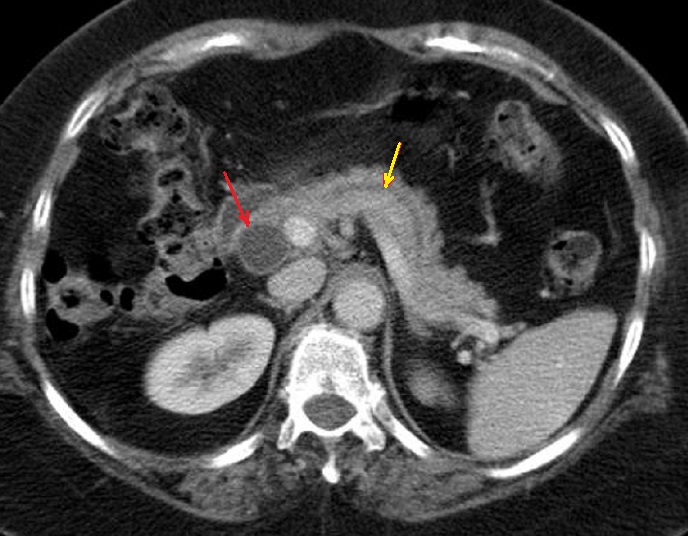

Image

radiologique TDM d'une adenocarcinoma de la tete du

pancreas en coupe axiale . Aspect lesionnel est un

masse hypodense a bord iregulier , l.a tete et le

corp du pancreas est deformation et tumefie .(

fleche rouge ) |

Parfois aspect lesionaire

est isodense ( fleche rouge ) . Par sa propiete de

moins de rehaussement de contrast intraveineuse

image radiologique du tumeur serait devenir nettete

sur les coupe TDM plus C+ . Image radiologique TDM

en coupe axiale ( n'a pas de contrast intraveineuse

) |

Aspect radiologique TDM d.'

une adenocarcinoma de la tete du pancreas , c'est un

masse tissulaire hypodensite a bord tres nette situe

a la tete du pancreas ( fleche rouge ) . Par

l'obtacle de la tumefaction le signe indirect

se presenter c'est image de dilatation en amont du

canal pancreatique principale ( fleche jaune ) |